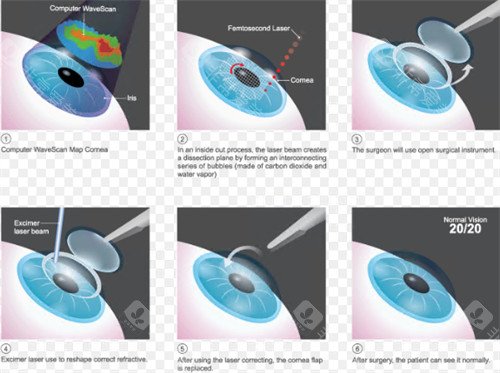

作为国内外规模比较靠前的眼科连锁机构,爱尔眼科在角膜交联领域优先实现三大技术升级:

免核黄素浸泡步骤,手术时长缩短至10分钟

采用370nm比较准紫外线,对角膜内皮零损伤

飞秒激光辅助移植吻合精度达0.01毫米

2016年优先引入经美国FDA认证的角膜交联系统,2025年升级至第五代设备,紫外线能量控制精度高。

术前:采用Pentacam三维眼前节分析仪进行角膜生物力学评估